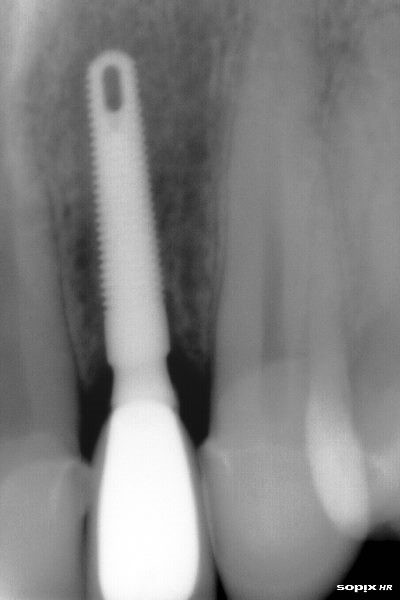

Radiografía de un Implante